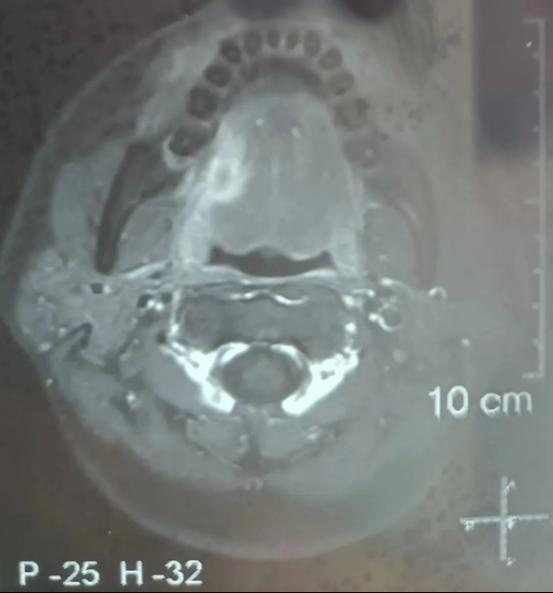

今年34岁的患者因“右舌缘疼痛性包块3+月”到公司口腔颌面外科住院治疗,完善病理活检及颌面部MRI检查后明确为右舌缘鳞状细胞癌,临床分期为cT3N0M0,且肿瘤已侵犯右侧舌外肌。

术前图

患者颌面部MRI影像